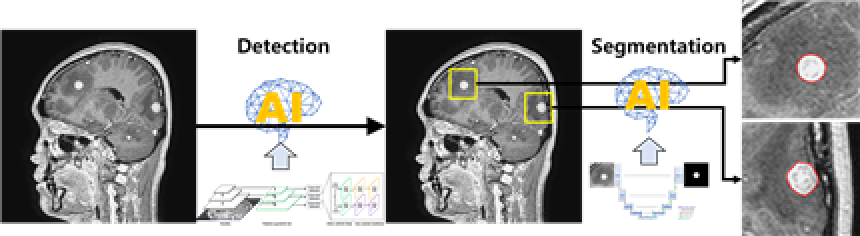

뇌전이암의 조영증강 뇌 MRI를 중심으로 뇌 CT 및 MRI를 이용하여 뇌전이암의 정확한 위치와 크기를 인식하기 위한 AI 시스템을 학습 시킬 수 있는 데이터셋 구축이 목표임

◦ AI 기반 뇌전이암 진단을 위한 다중모델 뇌 영상 데이터 구축 ◦ 뇌전이암 환자의 방사선 치료 설계 보조 인공지능 개발 활용

AI 모델 상세 설명서 다운로드 AI 모델 다운로드학습 알고리즘 RetinaNet 및 U-net 기반

RetinaNet과 U-Net을 함께 사용 또는 U-Net만 사용